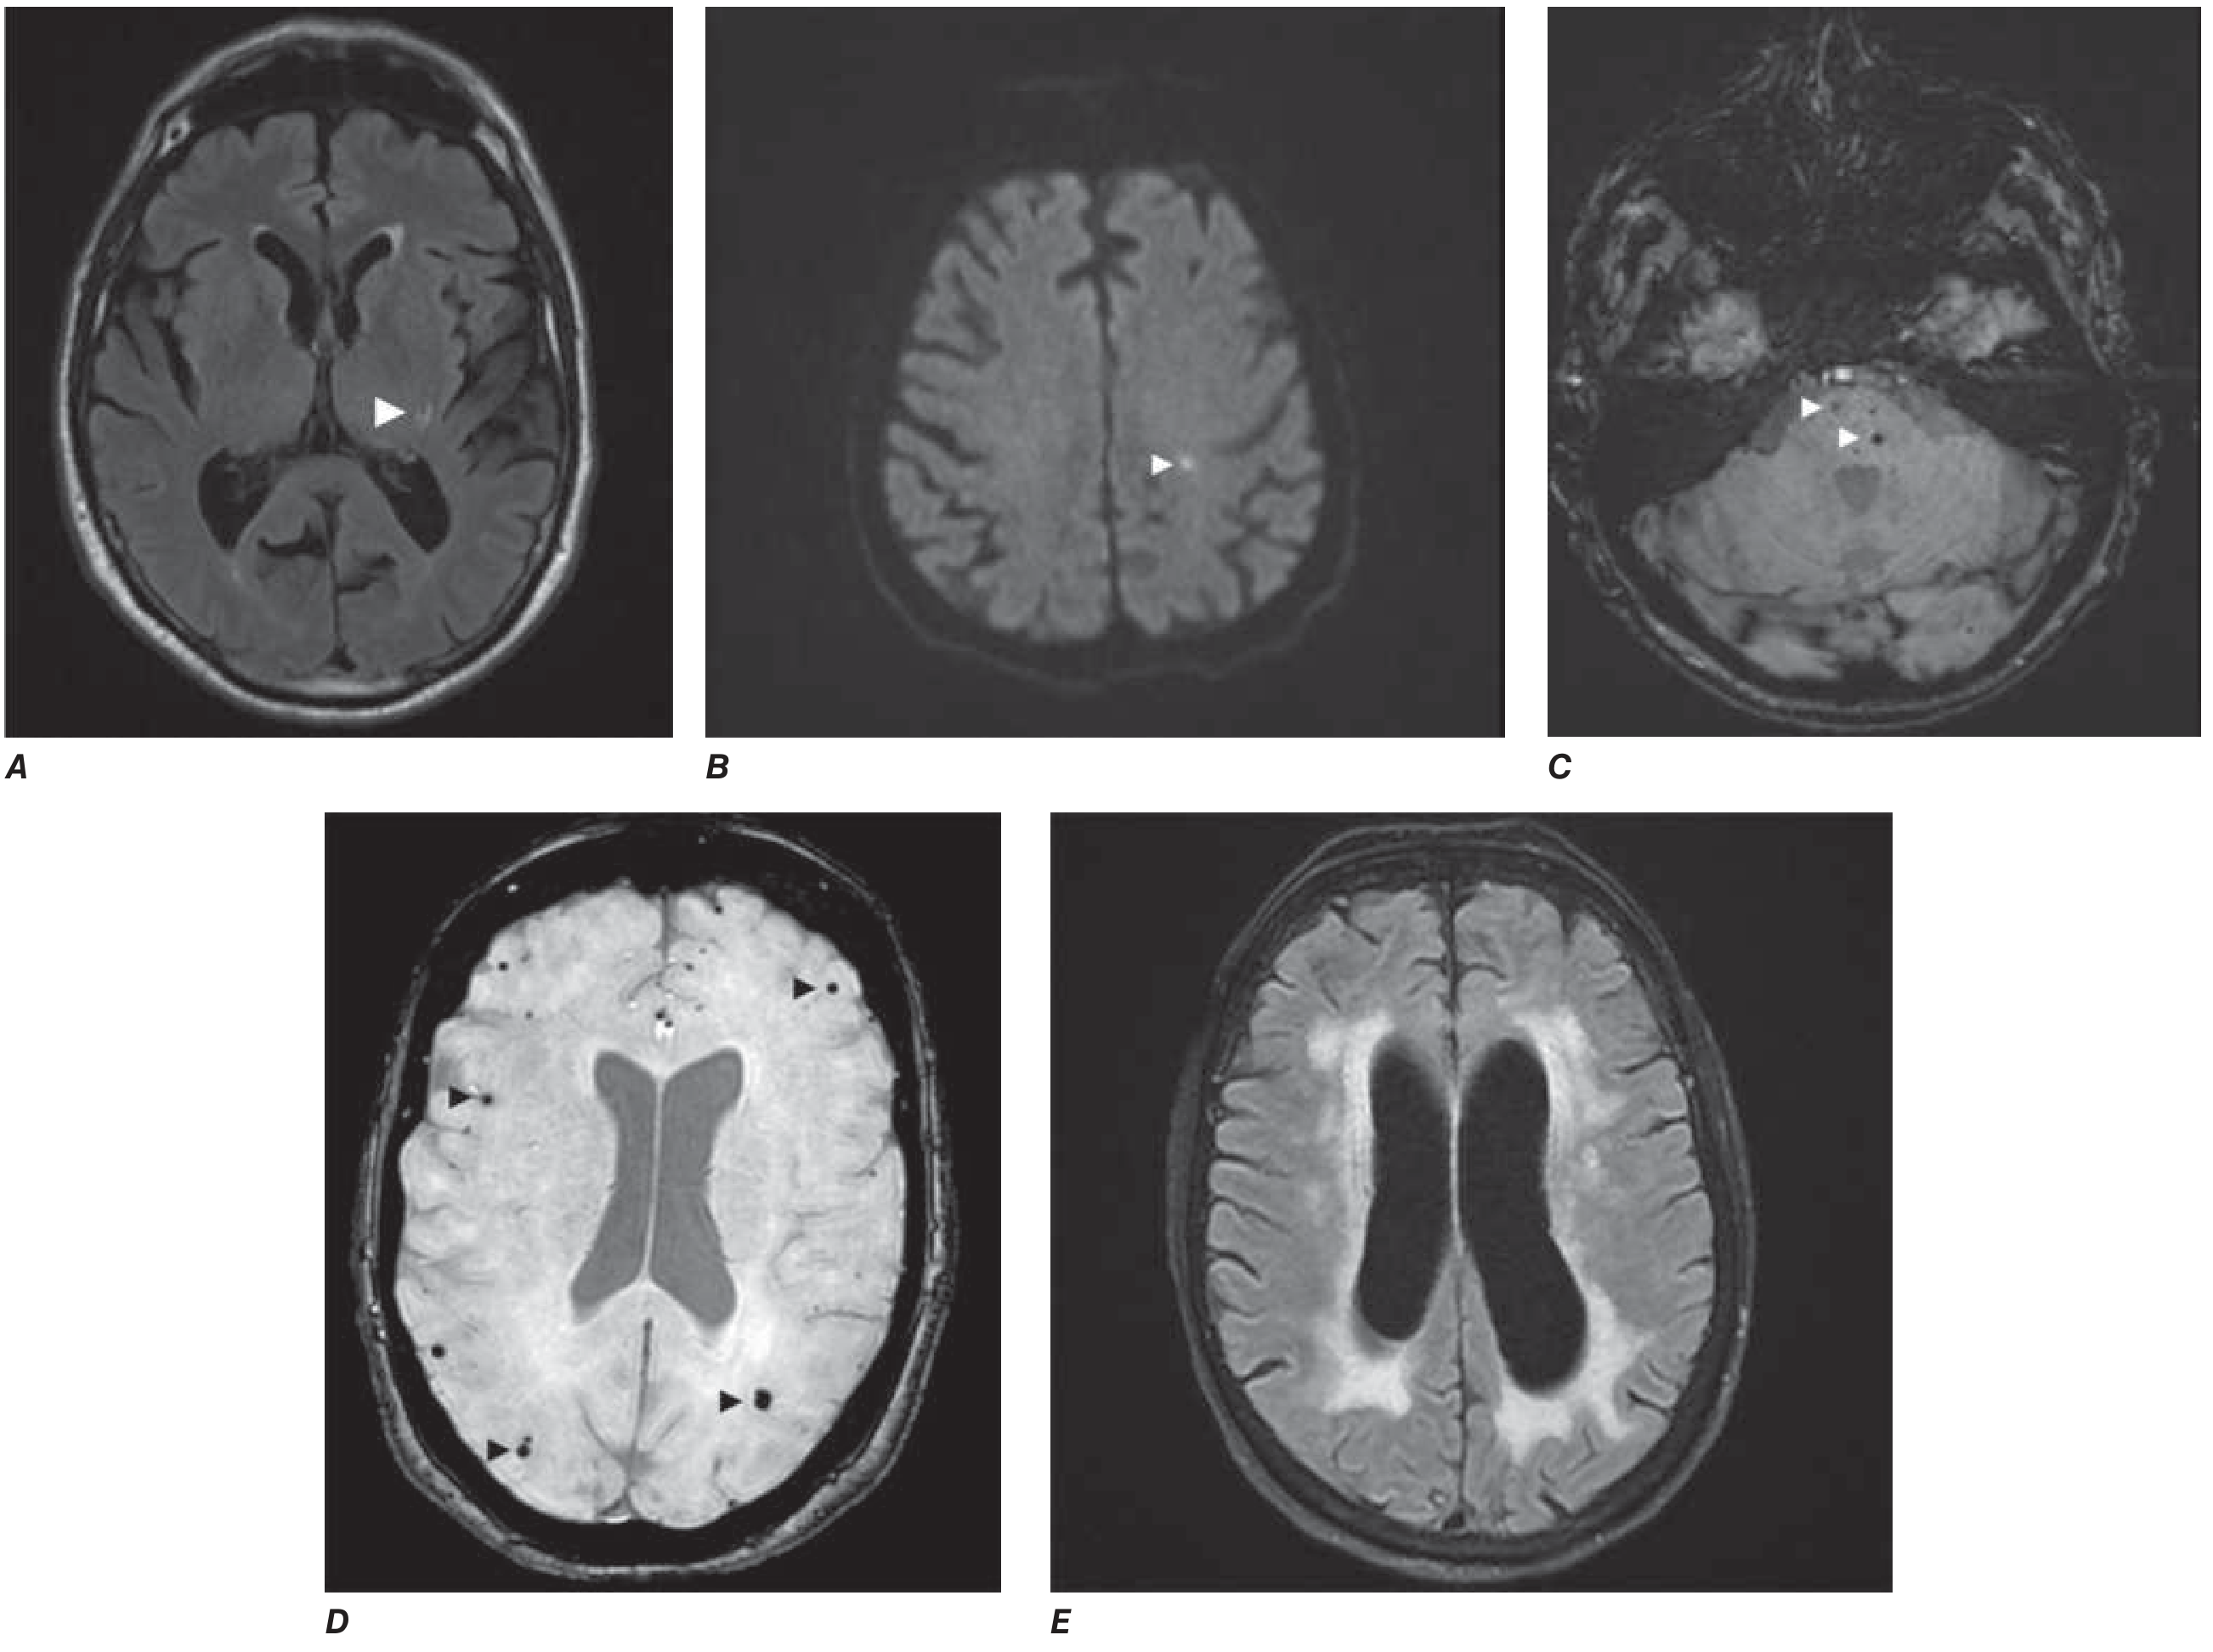

MRI markers of cerebral small vessel disease — lacunar infarct (A, left thalamus), acute microinfarct (B, centrum semiovale), white matter hyperintensities (E, confluent periventricular)

MRI markers of cerebral small vessel disease. A: Lacunar infarct (FLAIR, left thalamus). B: Acute microinfarct (DWI, centrum semiovale). E: Confluent white matter hyperintensities (FLAIR). — Harrison's Principles of Internal Medicine, 22E, Fig. 444-1